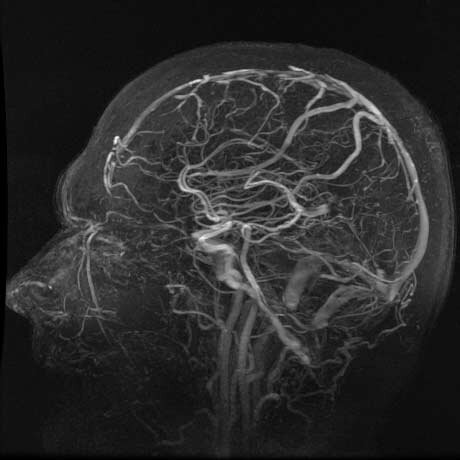

• ANGIOGRAFÍA

ANGIOGRAFÍA

Egas Moniz primera angiografía.